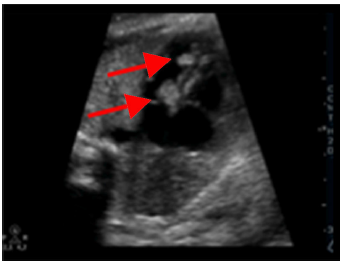

En la cavidad izquierda se identificó una imagen ecogénica (fig. 1) de bordes definidos, adherida a la pared septal del ventrículo izquierdo, de 11 × 8 mm y otras lesiones de iguales características aunque de menor tamaño ubicadas hacia el ápex ventricular izquierdo. El resto de la anatomía cardiaca no presentaba alteraciones estructurales. No se identificaron signos de descompensación hemodinámica como hidrops o derrames.

Figura 1 Se aprecian dos lesiones pendulares en el ventrículo izquierdo adheridas al septum.